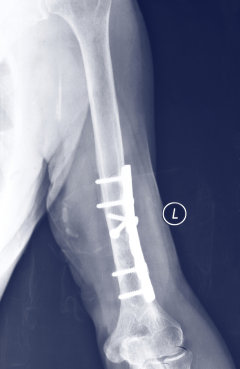

Schrauben aus Magnesium-Kalzium-Legierungen, wie im Bild rechts, können vom Körper problemlos abgebaut werden und sind dabei leicht und fest zugleich. Foto: HZG/ Martin Wolff

Am Helmholtz-Zentrum in Geesthacht besitzt man seit vielen Jahren große Kompetenz, um Prototypen von metallischen bioabbaubaren Implantaten aus Magnesium-Legierungen herzustellen und zu erforschen. Die Materialforscher untersuchen zum Beispiel neuartige Magnesium-Kalzium-Legierungen. Diese zeigen Werkstoffeigenschaften, die denen des Knochens ähneln, sie sind stabil und gleichzeitig elastisch. Kalzium scheint als Legierungselement gut geeignet zu sein, da es sich genau wie Magnesium zu ungiftigen Produkten im Körper abbauen könnte. Die Abbauprodukte könnten sogar das Knochenwachstum stimulieren.